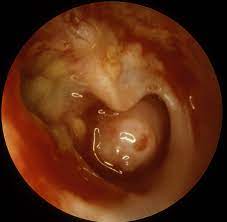

Chronic Suppurative Otitis Media With Acquired Cholesteatoma

Chronic Suppurative Otitis Media With Acquired Cholesteatoma from cdn0.scrvt.com

Chronic suppurative otitis media (csom) is one of the leading causes of preventable disabling hearing impairment (dhi) in developing countries. It is characterized by chronic drainage from the middle ear associated with tympanic membrane (tm. Acute otitis media and blockage of a eustachian tube are among the causes of chronic suppurative otitis media. Complications include development of aural polyps, cholesteatoma, and other infections. There will be a purulent discharge through a perforated tympanic membrane present for more than 6 weeks, conductive hearing loss and often, inflammation of the mastoid cavity. Chronic suppurative otitis media (csom): 1) perforation of the tympanic membrane due to acute infection or tympanotomy tube, 2) discharge from the middle ear (otorrhea), and 3) prolonged duration (;gt;2 wk). Csom occurs following an upper respiratory tract infection that has led to acute otitis media.

Complications include development of aural polyps, cholesteatoma, and other infections.